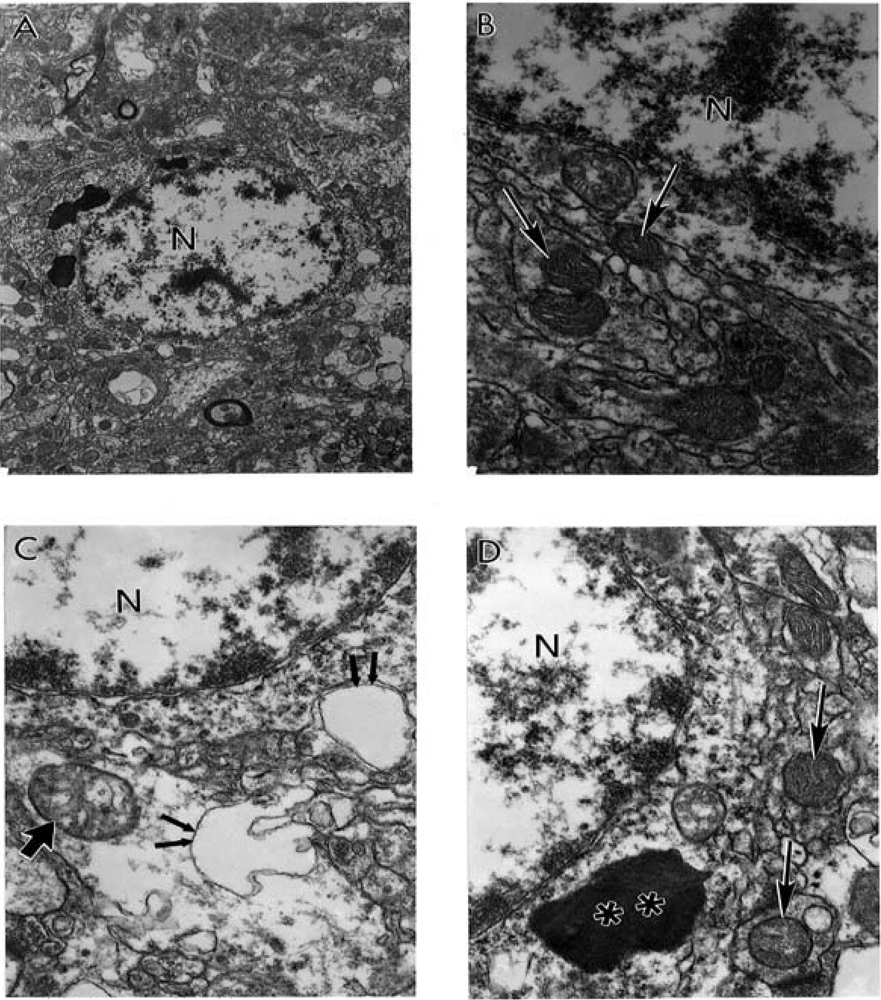

6.2. Cerebrovascular Lesions Observed During Ischemia/Reperfusion Induced Oxidative Stress